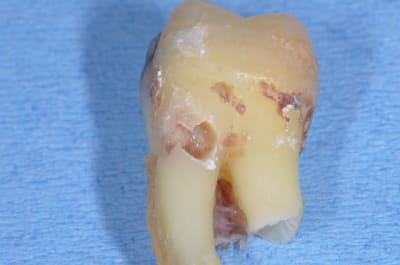

C'est une image typique de résorption externe, ci joint un cas récent d'un confrère qui me demandait mon avis également sur le même type de lésion, il m'a transmis la photo de la dent après l'extraction. La décision d'extraire a été prise car une atteinte osseuse de la furcation commençait. La dent était elle complètement asymptomatique et répondait tout à fait normalement au test de vitalité, car la résorption externe préserve en général le tissus pulpaire